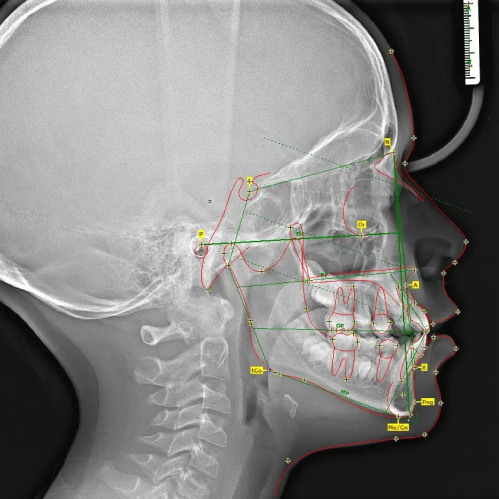

Дозволяє оцінити скелетні співвідношення і провести необхідні вимірювання для корекції основних відхилень у структурі зубо-щелепної системи.

500 ₴

Дозволяє оцінити скелетні співвідношення і провести необхідні вимірювання для корекції основних відхилень у структурі зубо-щелепної системи.